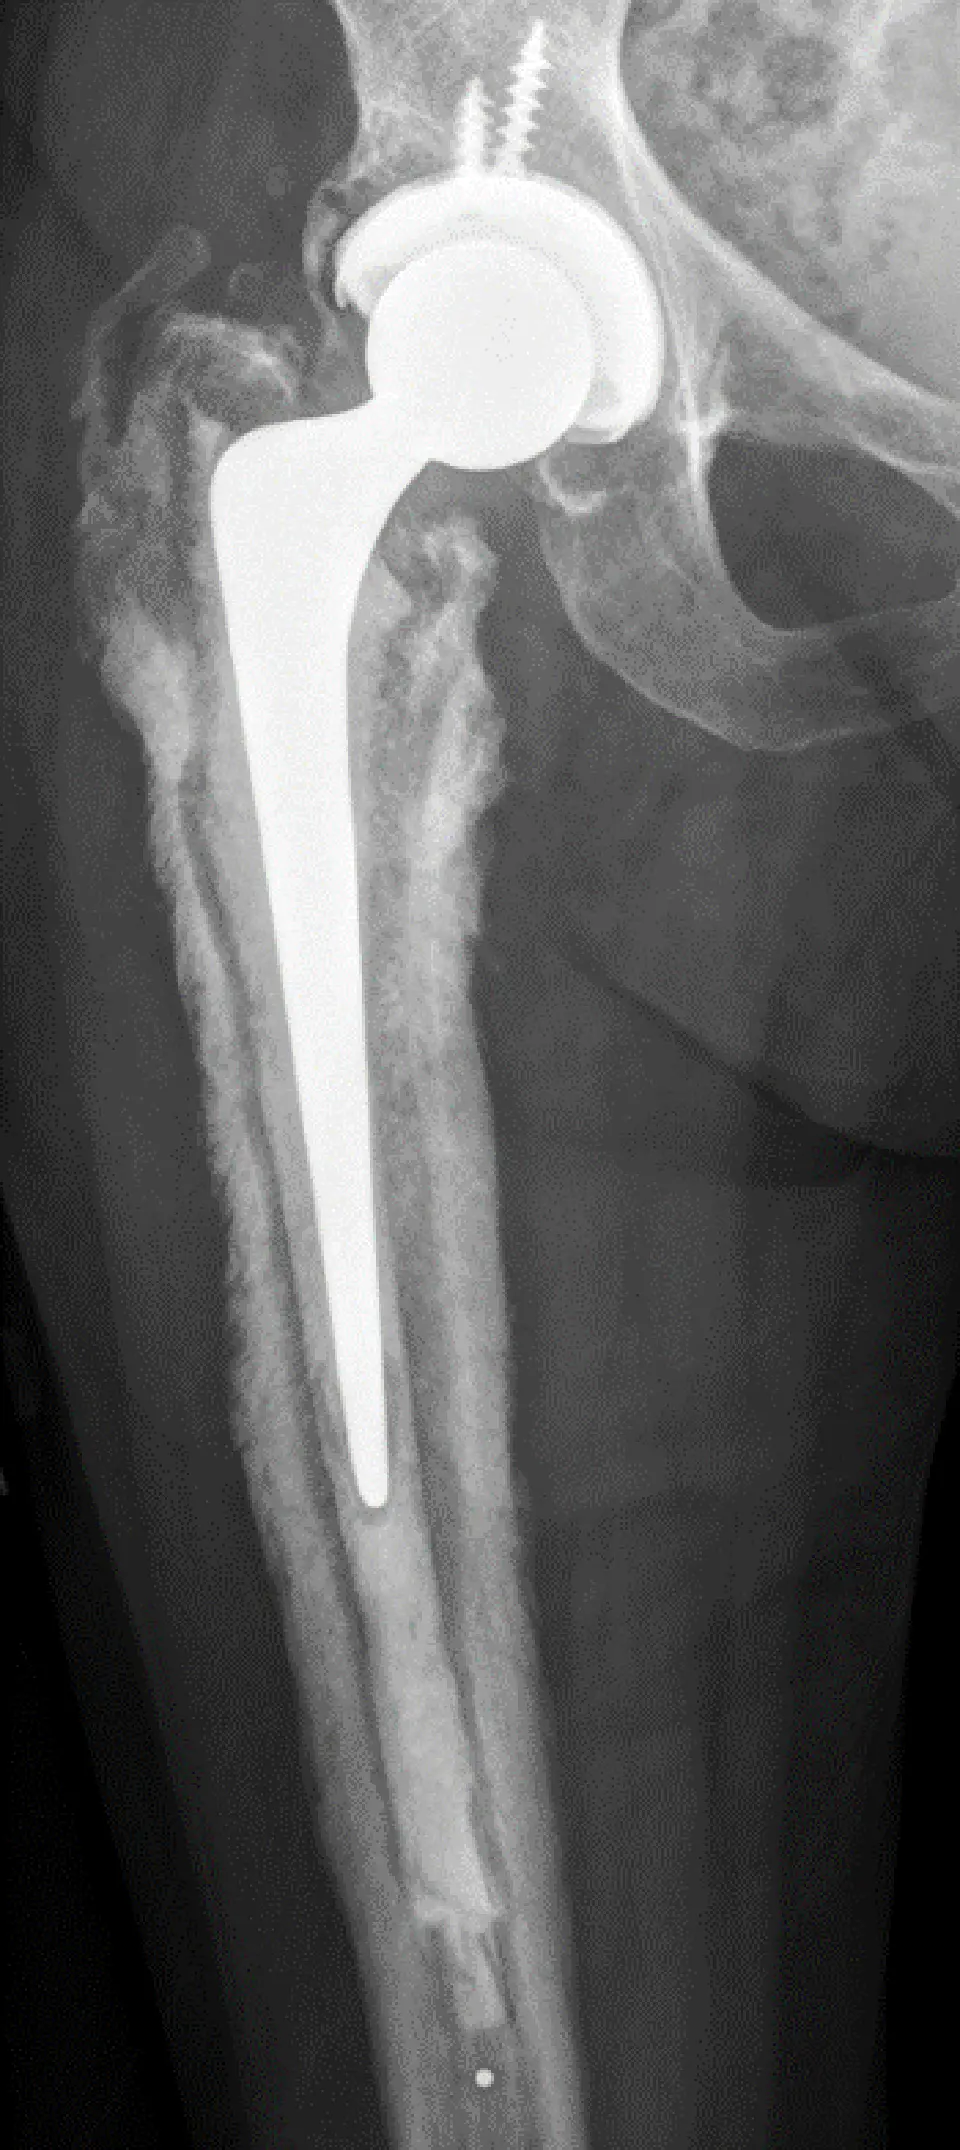

Infected Total Hip Replacement

Infection in a total hip replacement is a devastating complication. It occurs in 1:200-300 hip replacements and can occur early (within the first 12 weeks), delayed (within a year) or late (any time from a year onwards – even at 20 years down the line). It almost always requires surgical treatment to resolve and often requires complete removal of the infected hip replacement. Treatment for this is rarely done in the private hospital setting due to the complexity of the problem and its management. If this is something that you are concerned about, I would be happy to see you for an initial consultation and investigations but the majority of your care would be performed in our specialist Prosthetic Hip Joint Infection Clinic at Southmead Hospital. This clinic is run by me and 4 other specialist surgeons together with a number of microbiologists who all work together to achieve the best outcomes for this challenging problem. Referral to this clinic is normally via other hip surgeons or GPs.